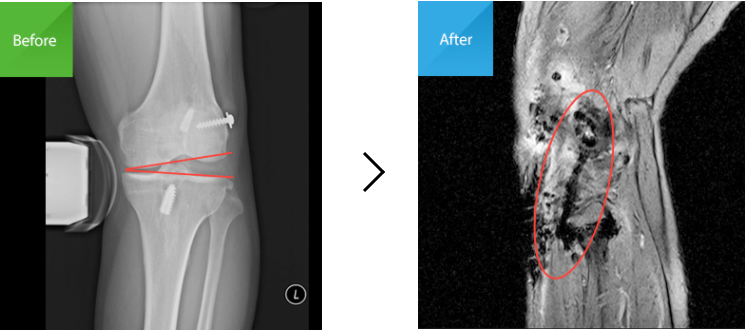

수술 전 : 외측측부 인대가 파열되어

상하 뼈가 벌어져 있는 상태임(X-RAY)

수술 후 : 파열되어 있는 인대에 타가건을 이용해,

삼각형 모양으로 재건해 둔 상태임(MRI)